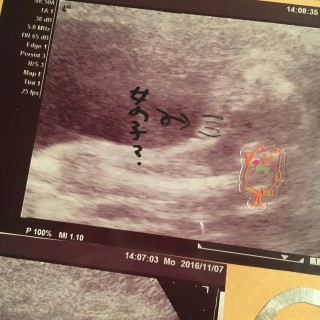

頭の大きさは5センチ以上になってました。 胎動も少しづつわかるように(^ω^) そして性別。 女の子みたいです!ネットの性別判断(つわりが少なければ男とか右の脈が強ければ女~とか医学的根拠が無いらしいアレです笑)それでは完全に男だったのに! やっぱり関係無いのかなー? しかしまだ確定じゃないので隠している可能性もあります(*^o^*)どちらでも良いので早く性別が知りたい!!! 行っている病院では2Dエコーしか無いので再来週に違う病院にて4Dエコーしてもらいます。 その時に性別わかるかな笑